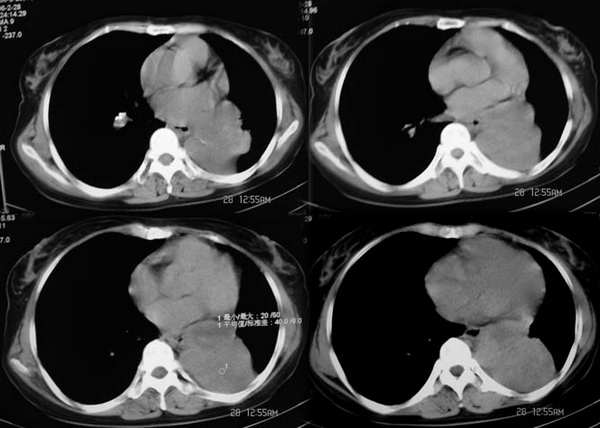

标题: CT2875:左下肺占位,请分析。

女,56y,左下肋缘下痛疼二月余

左侧胸廓容积缩小,纵隔左移,左下肺支气管闭塞.考虑中心型肺癌并左肺下叶不张,建议纤支镜.

属典型的左下肺中央型肺癌——左下分叶状肺肿块、支气管阻断、左下肺不张,纵隔淋巴结肿大。

左侧肺部体积缩小,纵隔向患侧偏移,左下肺支气管阻塞,中央型肺癌合并肺不张可能性大。

左下肺团块状软组织密度影,呈分叶状,边界清,未见小毛刺,左下肺支气管阻塞,纵隔见肿大淋巴结,考虑左下肺中央型肺癌伴纵隔淋巴结肿大,建议支纤镜检查。